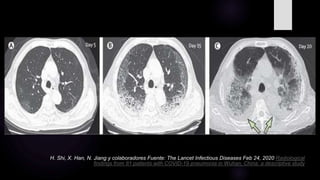

H. Shi, X. Han, N. Jiang y colaboradores Fuente: The Lancet Infectious Diseases Feb 24, 2020 Radiological

findings from 81 patients with COVID-19 pneumonia in Wuhan, China: a descriptive study

 Durante los días 0 – 2, lo predominante fue una TC normal en algo más de la mitad de los

casos y en un 44% de pacientes se encontró opacidad en vidrio esmerilado, generalmente

unilateral.

 Posteriormente, a los días 3 – 5, el hallazgo predominante fue opacidad en vidrio

esmerilado en un 88% de los pacientes seguido por consolidaciones, la afectación fue en

un 30% multilobar.

 A los días 6 -12, el hallazgo predominante fue opacidad en vidrio esmerilado con un

aumento en la frecuencia de consolidaciones, la afectación multilobar llegó al 50%.